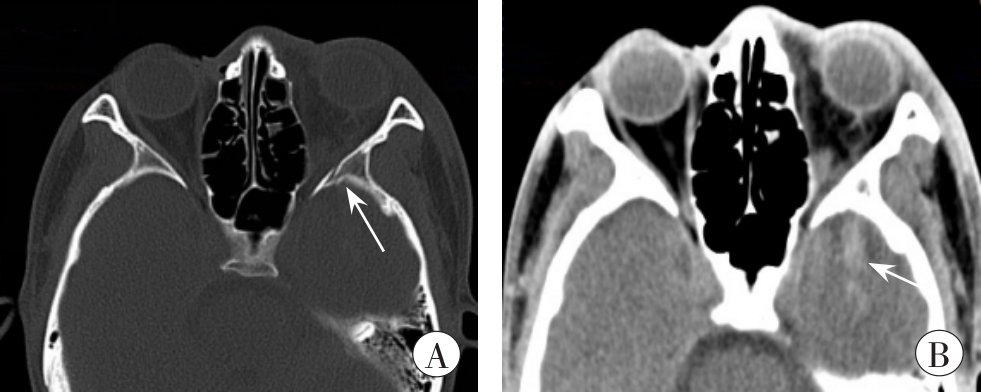

图3 受伤当日的头颅、眼眶CT图像

A:左眼眶外侧壁近眶尖处骨折(箭头所示);B:左颞叶脑挫裂伤(箭头所示)

Fig. 3 CT images of head and orbit on the day of injury